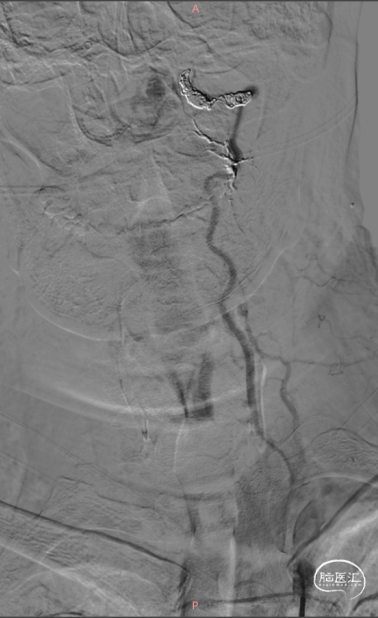

术前DSA

右椎动脉逆向血流,往CCJ AVF供血

既往闭塞的左椎动脉,血流复流往CCJ AVF供血

右侧椎动脉3D旋转,明确CCJ AVF的瘘口及引流静脉